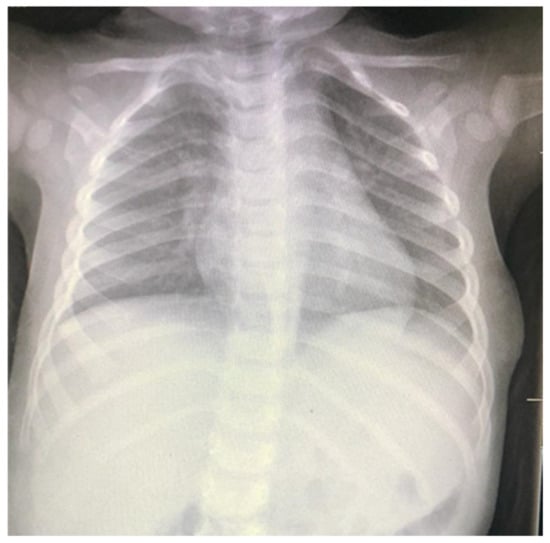

Sudden Appearance of a Palpable Chest Wall Mass Secondary to Macrocystic Lymphatic Malformation: A Case Report

2. Case Report